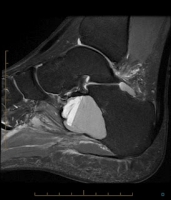

Aspect typique :

- Lésion lytique centrée métaphyso-diaphysaire chez un  jeune sans sclérose périphérique

Aspect Radiologique :

- Tumeur centrée ostéolytique, discrètement expansive (scalloping), métaphysaire ou métaphyso-diaphysaire

- taille moyenne 6-8 cm

- parfois lobulée

- contours nets, condensés (Ia)

- après fracture pathologique, "fallen sign"

- peut augmenter de taille avec le temps

- parfois calcifications dystrophiques

- réaction périostée qu'en présence d'une fracture pathologique